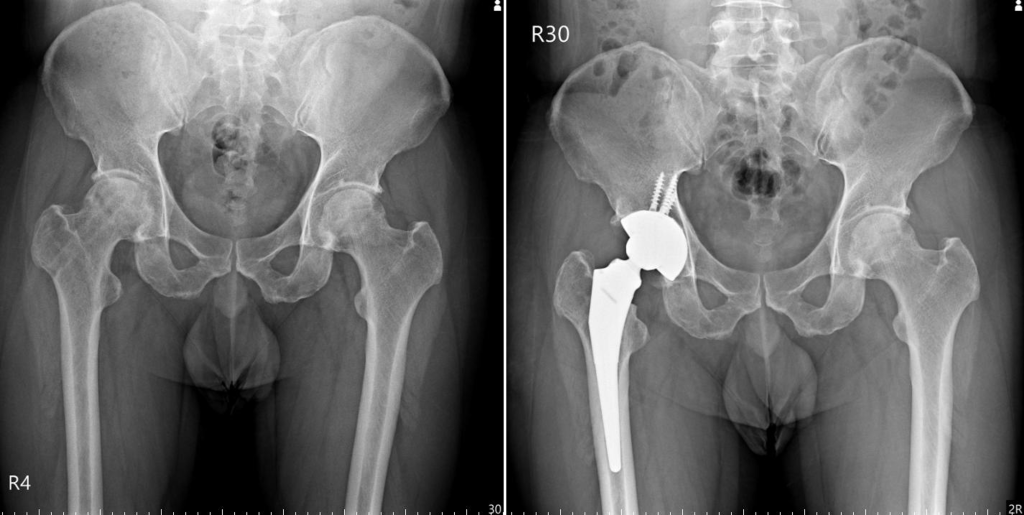

劉廷瑜醫師分享,「我曾收治一名40多歲的男性患者,他是一間麵店的老闆,每天都要站著工作好幾個小時,他來到我的診間時,已經確診為右側的股骨頭缺血性壞死,並且接受過一次減壓手術,他在減壓手術後第一個月右腳完全不能負重,第三個月開始恢復正常行走,到了術後半年發現髖關節還是疼痛不舒服,因而來找我評估進行人工髖關節置換手術」。

「因為他長期受到髖關節疼痛不適的困擾,很快就決定要動手術置換人工髖關節。經過專業評估及雙方討論,因為他的年紀較輕,活動量較大的他也希望降低術後髖關節脫臼或不穩定的風險,他選擇以『雙動式人工髖關節』搭配『鈦合金3D列印鈦骨髖臼杯』;再加上他想要盡快回歸工作,希望手術傷口比較不明顯,他選擇以『比基尼微創切口』的術式來進行手術」,劉廷瑜醫師說,「術後兩週回診檢查手術傷口時,我問他『枴杖呢』,他回答我說,他出院就不必使用枴杖輔助了,回診時也已經回到麵店的工作崗位了。」每位患者的病情總會有所差異,如果感到疼痛甚至影響正常生活,可以尋求專業醫師的建議,希望每位患者都有機會尋找到適合自身的治療方案。

病例分享:手術前 VS 手術後的比較